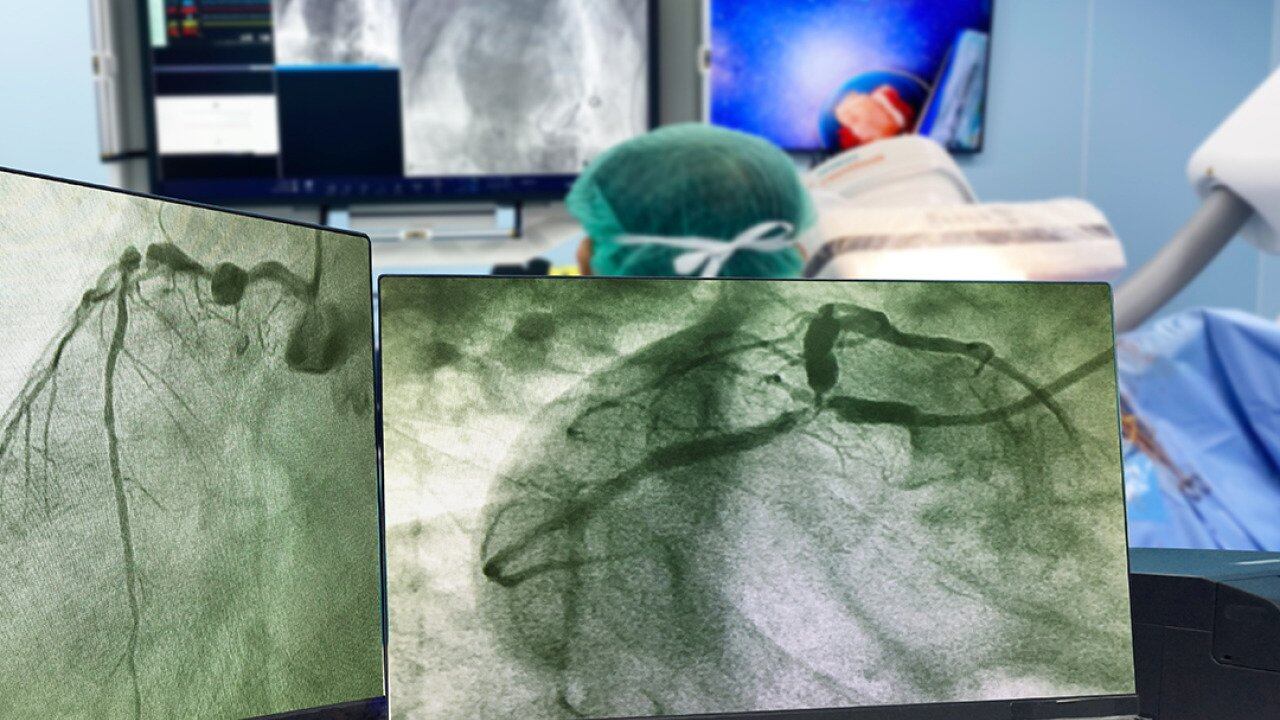

Malin thought he'd covered all the bases. But at a visit with his primary care doctor in early 2023, the grandfather of one mentioned a new development — dull, come-and-go pain in his left shoulder and arm when exercising. He soon found himself getting an electrocardiogram (EKG) to gauge his heart's electrical activity and an exercise stress test with nuclear imaging. Northwell Health cardiologist Jeffrey Kuvin, M.D., looked at Malin's risk factors, symptoms and test results and quickly set up a coronary angiogram.

The results made the scope of Malin's heart problem stunningly clear: He had a 99% blockage of his left anterior descending (LAD) artery. A heart attack originating in the LAD is sometimes called a "widowmaker" because the artery plays such a key role in supplying blood to the heart. The interventional cardiology team fixed the problem on the spot, inserting a mesh stent in Malin's LAD to prop it open. Six hours later, Malin went home, healthy, grateful and ready to adopt the medications and lifestyle changes his doctors advised.

“I’ve got pictures of my heart that clearly show the before and the after,” says Malin. “It’s very alarming how close I was to a tragedy.”

Coronary angiogram

Why you might need it: You're having new or worsening symptoms suggestive of heart disease or received abnormal test results that require further investigation.

How it works: A flexible tube called a catheter is inserted into an artery in your wrist or groin and threaded to the coronary arteries in your heart. Dye is injected to make it easier to get a detailed view of blood vessels on an X-ray image called an angiogram. You'll likely get a light sedative to help you relax. As with Malin, results might lead to the immediate placement of a stent; a short hospital stay may be required.

What it shows: It can detect restricted blood flow to the heart.